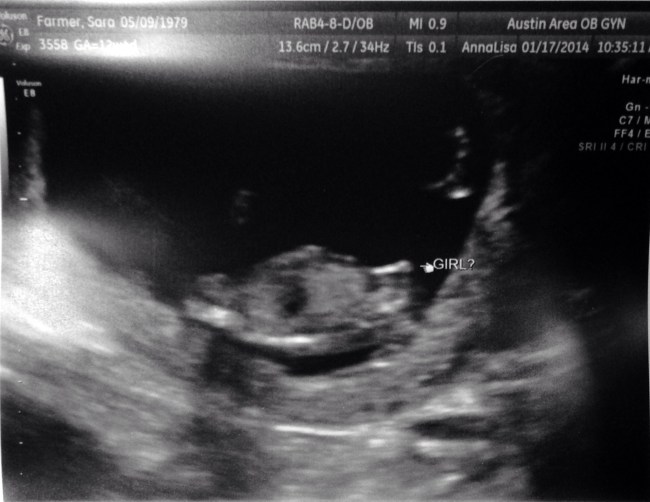

“No Y chromosome was detected. This is consistent with a female fetus.”

Those clinical, carefully ambiguous words filled me with incredulous joy. It’s a GIRL, folks! A healthy girl!! She is still too small for us to get a good look at her heart, but we have successfully cleared another hurdle. She is still alive and chromosomally normal at 15 weeks!

The test is incredibly accurate, though. The last ultrasound tech said she was 80% sure it’s a girl. I’ve had a gut feeling it was a girl for most of the pregnancy. (My gut has not been wrong yet, as far as I know. We never got to find out with Baby Bean.) The nurse at the doctor’s office said she calls it, “The 100% test”.